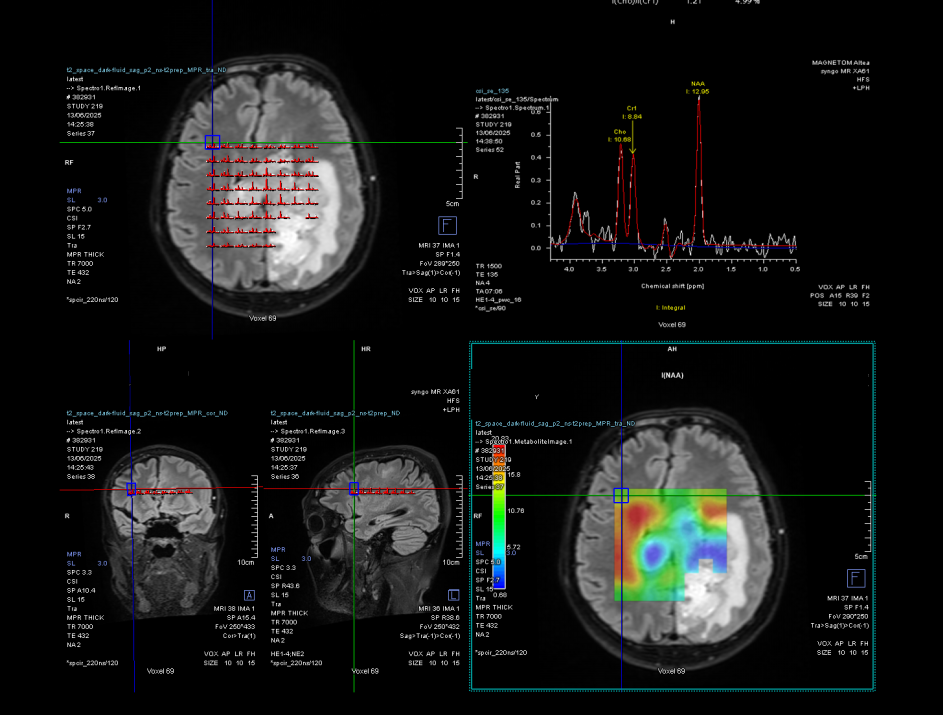

Pe lângă secvențele convenționale, tehnicile avansate aduc informații suplimentare:

- perfuzia evidențiază angiogeneza tumorală

- spectroscopia reflectă metabolismul celular

- DTI (tractografia) arată relația cu tracturile din substanța albă

Cu toate acestea, niciuna dintre aceste metode nu poate delimita complet infiltrarea microscopică. De aceea, planificarea chirurgicală și terapeutică trebuie să țină cont de această limitare.